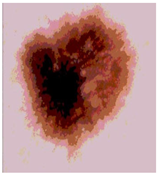

![]() | ![]() | ![]() | ![]() |

| Img1 | --- Pixel Intensity (0–255) ---> | ||

| Img2 | --- Pixel Intensity (0–255) ---> | ||

| Img3 | --- Pixel Intensity (0–255) ---> | ||

| Img4 | --- Pixel Intensity (0–255) ---> | ||

| Img5 | --- Pixel Intensity (0–255) ---> | ||

| Img6 | --- Pixel Intensity (0–255) ---> | ||

| Img7 | --- Pixel Intensity (0–255) ---> | ||

| Img8 | --- Pixel Intensity (0–255) ---> | ||

| Img9 | --- Pixel Intensity (0–255) ---> | ||

| Img10 | --- Pixel Intensity (0–255) ---> | ||